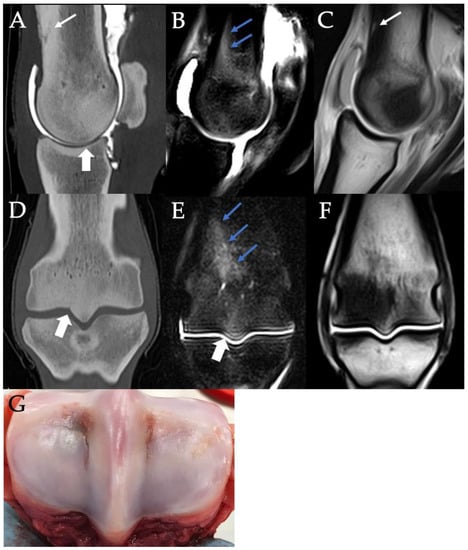

3.2. Sclerosis of the Subchondral and Adjacent Medullary Bone of the PSGs

3.3. PSG Subchondral Bone Lysis

3.4. PSG Subchondral Bone Defects

3.5. PSG Cartilage Defects

3.6. PSG STIR Hyperintensity

3.7. Combinations of PSG Pathology